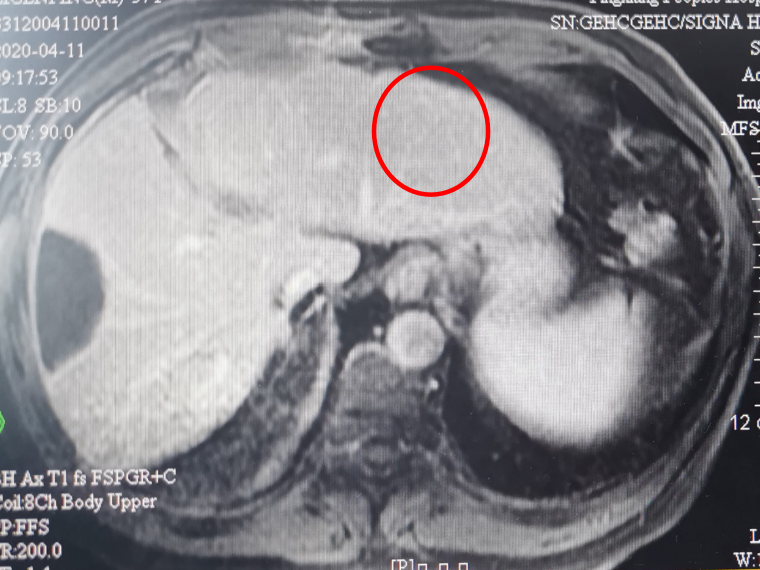

(1)联合治疗2周期

疗效评价:PR

本例患者为原发性肝细胞癌切除术后,术后行第一次TACE治疗病情平稳。但术后2个月复查发现肝内新发占位、AFP动态快速升高,考虑复发,予以第二次TACE治疗,病情未得到控制,考虑疾病进展。患者ECOG PS评分1分、Child Pugh A级,身体基线情况较好,于我院就诊后考虑予以免疫联合靶向治疗。为观察并监测药物毒副作用,先行予以靶向药物治疗,不良反应为轻度腹泻,患者可以耐受。靶向治疗1个月后加用替雷利珠单抗免疫治疗,用药2周期疗效即达PR,AFP明显下降。截至最近一次随访,患者的靶病灶完全消失,AFP降低至正常,疗效达到CR,PFS已达6个月。用药期间,患者除轻度的血小板下降之外,无明显主观不良反应。